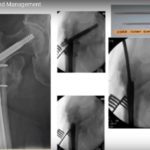

Tension Band Principles for the FRCS Tr&Orth

Courtesy: Quen Tang, FRCSOrth, UK